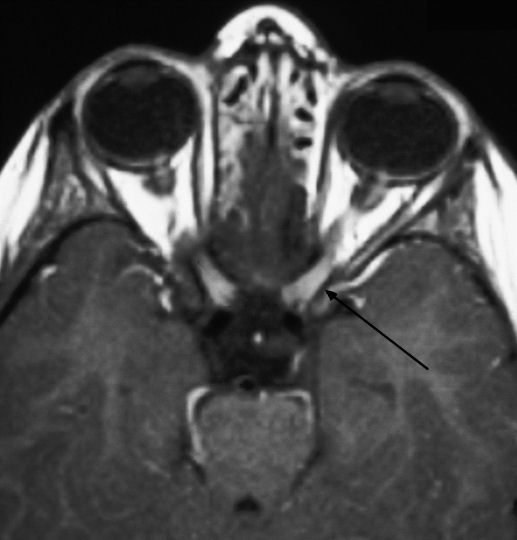

Immunological tests for ANA titer were 1:320, tests for anti-ENA, anti-dsDNA, anti-cardiolipin, anti-β2GPI, lupus cells, antibodies to GAD65, IA-2, insulin and cryoglobulins were negative. MRI brain and whole spine revealed 1) hyperintensity in cervical cord C5 to C7 level (Figure 1 [Fig. 1], Figure 2 [Fig. 2], Figure 3 [Fig. 3]); 2) hyperintensity in the thoracic cord till T12 level (Figure 4 [Fig. 4], Figure 5 [Fig. 5], Figure 6 [Fig. 6]); 3) hyperintensity in the right optic nerve head (Figure 7 [Fig. 7]). The clinical features and investigations (NMO IgG was positive) fit into the criteria of neuromyelitis optica. The thyroid profile was suggestive of hypothyroidism (Table 3 [Tab. 3]). Laboratory studies confirmed the presence of antithyroid antibodies (Table 4 [Tab. 4]). Fine needle aspiration of the thyroid showed lymphocytic infiltration of the thyroid gland (Figure 8 [Fig. 8], Figure 9 [Fig. 9]). The patient was treated with prednisolone 1 g/day for 5 days and azathioprine (2.5–3 mg/kg/daily). The patient showed improvement in motor symptoms and sensory symptoms approximately by 60% after a period of 2 months of treatment. Patient was started on thyroxine 50 μg and later dosage was increased to 100 μg.

Figure 7: MRI brain showing hyperintensity in the right optic nerve head